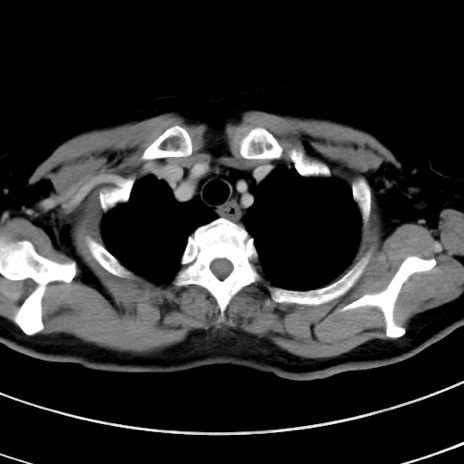

症例9(横断像)

【症例】 60歳代女性

【主訴】むかつき、みぞおちの痛み

【現病歴】3日前よりむかつきがあり、食事がとれない。

【既往歴】糖尿病

【身体所見】発熱なし、心窩部圧痛軽度あるも、腹膜刺激症状なし。

【データ】WBC 7400、CRP 1.92